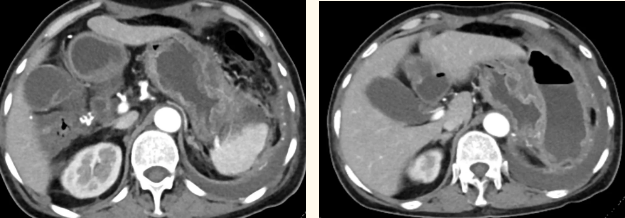

一籌莫展的她終于在病友的介紹下,來(lái)到西安國(guó)際醫(yī)學(xué)中心醫(yī)院找到蔡磊主任。經(jīng)過(guò)詢(xún)問(wèn)病史,查體等,蔡磊主任建議口服索坦治療。3個(gè)月后,李阿姨復(fù)查CT提示胃間質(zhì)瘤較前明顯縮小,大小約10.4cm?6cm。但仍存在消化道出血,營(yíng)養(yǎng)狀況差,全身無(wú)力,骨髓抑制。蔡磊主任隨即將患者收治入院。